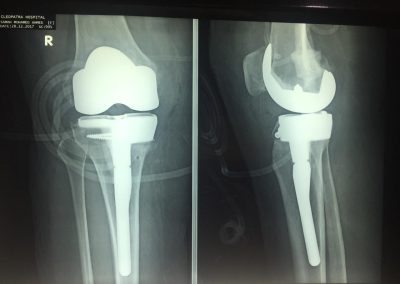

صوره لتاكل شديد جدا بالركبة مع وجود نقص شديد بالجزء الداخلي لأعلى عظمة الساق.